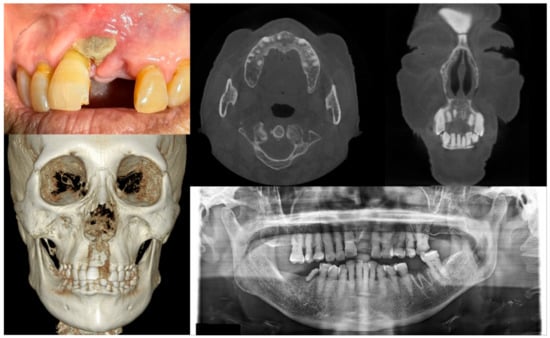

Figure 3.

Case 3 with MRONJ Stage 2: Clinical photo, panoramic view, and computed tomography imaging including three-dimensional reconstruction showing exposed alveolar bone with pus discharge on the right mandibular posterior area. A 68-year-old female patient with a history of intravenous administration of ibandronate for eight years and intravenous administration of denosumab for the last year complained of facial swelling, severe pain, and pus discharge. She had undergone extraction of the right lower second molar at the private dental clinic to relieve the facial swelling and pain. Symptoms were relieved slightly after extraction but worsened again after two weeks. As a result of the examination, exposed bone and infection signs were observed.